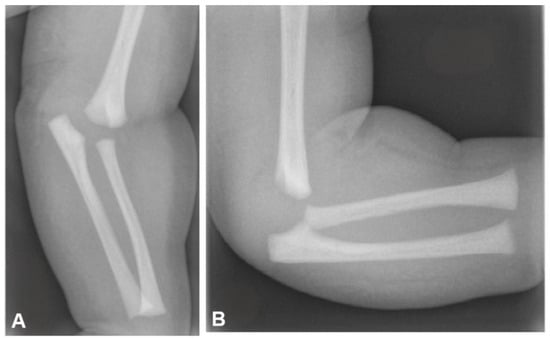

On plain radiographs, indirect signs of elbow intraarticular fractures such as joint effusion and soft tissue swelling may not always be apparent [36] (Figure 2).

Figure 2. Plain elbow X-rays showing distal humerus physeal separation in an infant. Note that secondary ossification centers have not been ossified. (A) Anteroposterior view, (B) lateral view.

Although the physeal part of DHPS may remain undisplaced in relation to the humerus, a posteromedial or medial translation of the ulna is commonly observed [32]. Interestingly, anterior displacement of the epiphysis has also been reported [42]. In newborns and infants with unossified epiphysis, ultrasonography can be a valuable diagnostic tool, especially if plain radiographs are negative or inconclusive [43]. Magnetic resonance imaging (MRI) not only confirms the diagnosis in challenging or unclear cases, particularly when the distal region of the humerus has not been still ossified, but also shows the presence and extend of concurrent injuries [30]. In the present study, we found that ultrasound and MRI examinations were utilized in 16% and 4% of cases, respectively, due to the inherent difficulty in establishing the diagnosis. We believe that ultrasonography and MRI screening should be routinely integrated in the diagnostic protocol when a high suspicion of distal humerus injury and normal elbow radiographs is apparent.